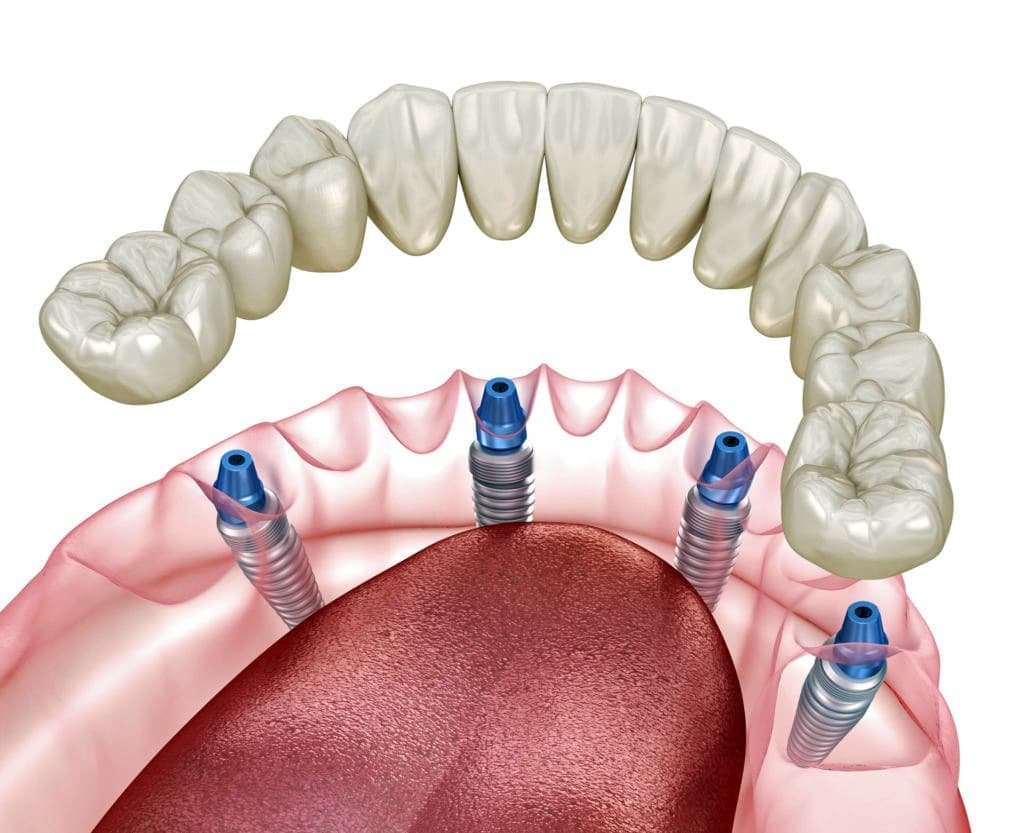

インプラントとは、顎の骨に人工歯根となる金属を埋め込み、その金属を土台にして、天然の歯と同じような人工の歯を取り付ける治療方法です。

オールオン4は、奥のインプラントを骨のある部分へ斜めに埋め込み力を広く均等に分配することにより、最小4本のインプラントで全ての人工歯を支えることができる術式です。